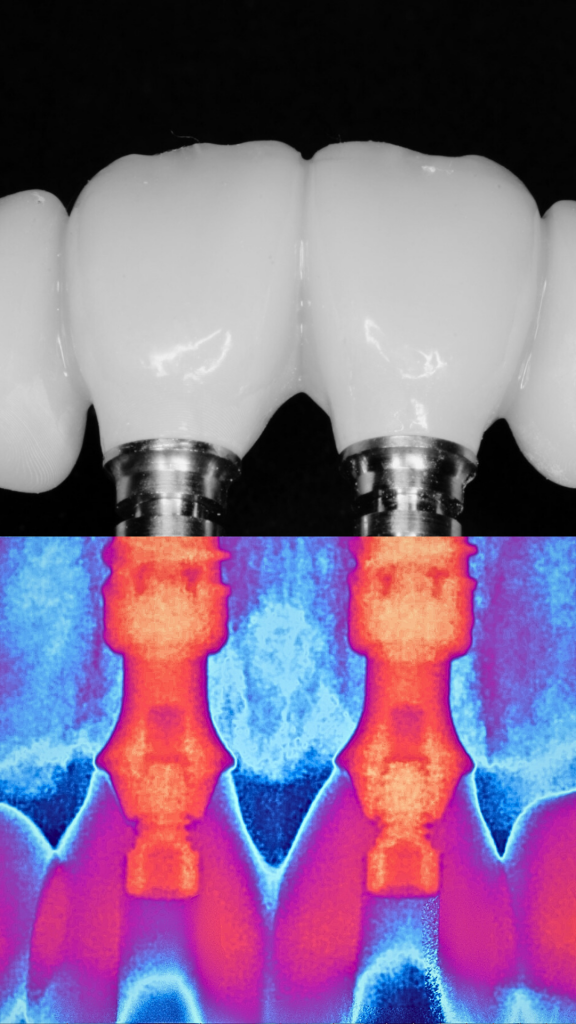

Cirugía Guiada por Ordenador

En nuestra clínica, ofrecemos cirugía guiada utilizando software 3D exacto, una técnica innovadora que nos permite planificar con precisión la colocación de los implantes y asegurar su correcta integración en el hueso maxilar o mandibular. De esta manera, podemos garantizar una colocación precisa, sin errores y con un mínimo de molestias para el paciente.

Según un estudio publicado en el Journal of Dental Research, la tasa de éxito de los implantes dentales a los 10 años es del 90-95%. Este estudio se realizó con una muestra de más de 2.600 implantes en 132 pacientes y se llevó a cabo en múltiples clínicas dentales en Europa. Además, el estudio encontró que la tasa de éxito de los implantes aumenta a medida que el tiempo de seguimiento se extiende, lo que sugiere que los implantes pueden durar mucho más que 10 años con un buen cuidado y mantenimiento adecuado.

Durante la cirugía, se utilizan guías quirúrgicas personalizadas basadas en esta planificación digital. Estas guías ayudan a posicionar el implante en el lugar exacto determinado en la planificación, asegurando que esté perfectamente alineado y rodeado de suficiente hueso, lo cual es crucial para su integración y estabilidad a largo plazo. Además, esta precisión garantiza que el implante esté en la posición óptima para recibir la prótesis dental, lo que mejora la funcionalidad y estética del resultado final.